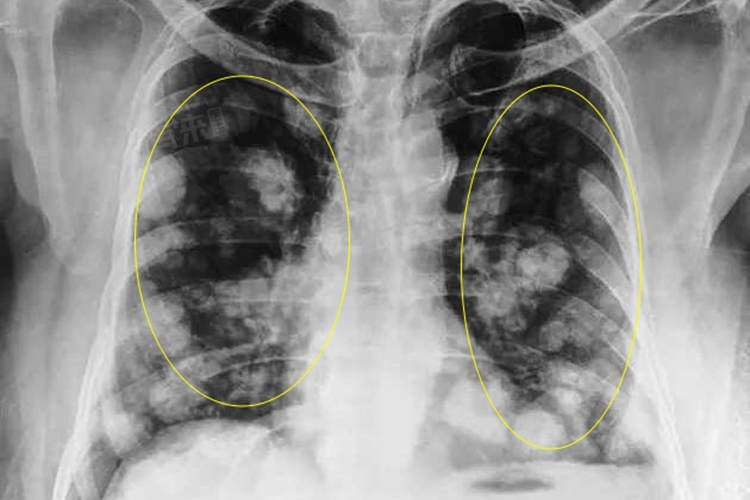

- 分类级别:LU-RADS3S类肺部结节属于LU-RADS分类系统中的3类,即未定性结节,是指该结节的影像学特征相对不典型,无法明确判断其性质是良性还是恶性。

- 恶性概率:LU-RADS3类结节的恶性概率相对较低,但并不意味着可以忽视该类结节,仍需要密切随访观察监测具体变化。